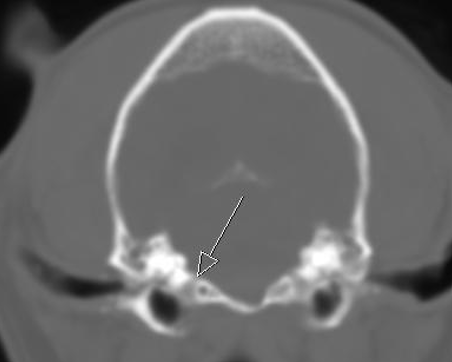

A orbital fissure

B rostral alar foramen leading to alar canal, round foramen inside the skull